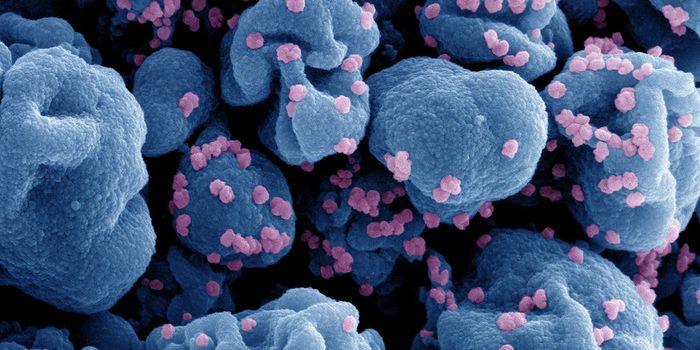

AUG 24, 2020ImmunologyOnce in the body, HIV tracks down T cells that bear the CD4 receptor. It attaches to these immune cells, fusing itself w ...